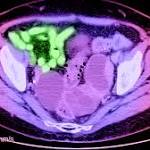

Report: Women Everywhere Don't Know Enough About Ovarian Cancer